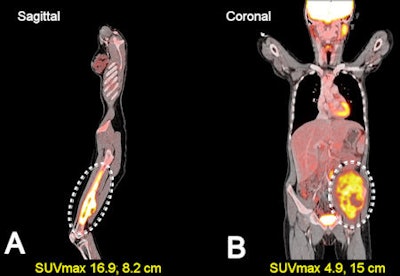

| Image A shows a 14-year-old patient with an osteosarcoma in the distal femur. The tumor exhibited a high SUVmax of 16.9. Image B is a coronal view of a 10-year-old with Ewing's sarcoma of the left hemipelvis with a lower SUVmax of 4.9. FDG uptake was heterogeneous in both tumors. The areas of low FDG uptake represent tumor necrosis. Images courtesy of Fran Franziska Walter, MD. |

The researchers measured and compared SUVmax in bone sarcoma and soft-tissue sarcoma cases, and the group found the 12 osteosarcoma cases to have generally the highest SUVmax readings among all cancers, with a mean of 10.1 and ranging from 4 to 21. The eight Ewing's sarcoma cases had a much lower SUVmax level, with a mean of 4 and a range from 1 to 9.

Among the soft-tissue sarcomas, the mean SUVmax was 4.4, with nine cases between 1 and 6. The highest SUVmax among all 30 tumors was the one case of angiosarcoma, which had an SUVmax of 24.